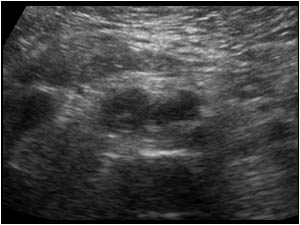

Huyết khối TM chủ dưới

Huyết khối TM chủ dưới - Ảnh 4

» Thông tin: Nữ giới – 68 tuổi.

» Lâm sàng: Sưng phù chi dưới.